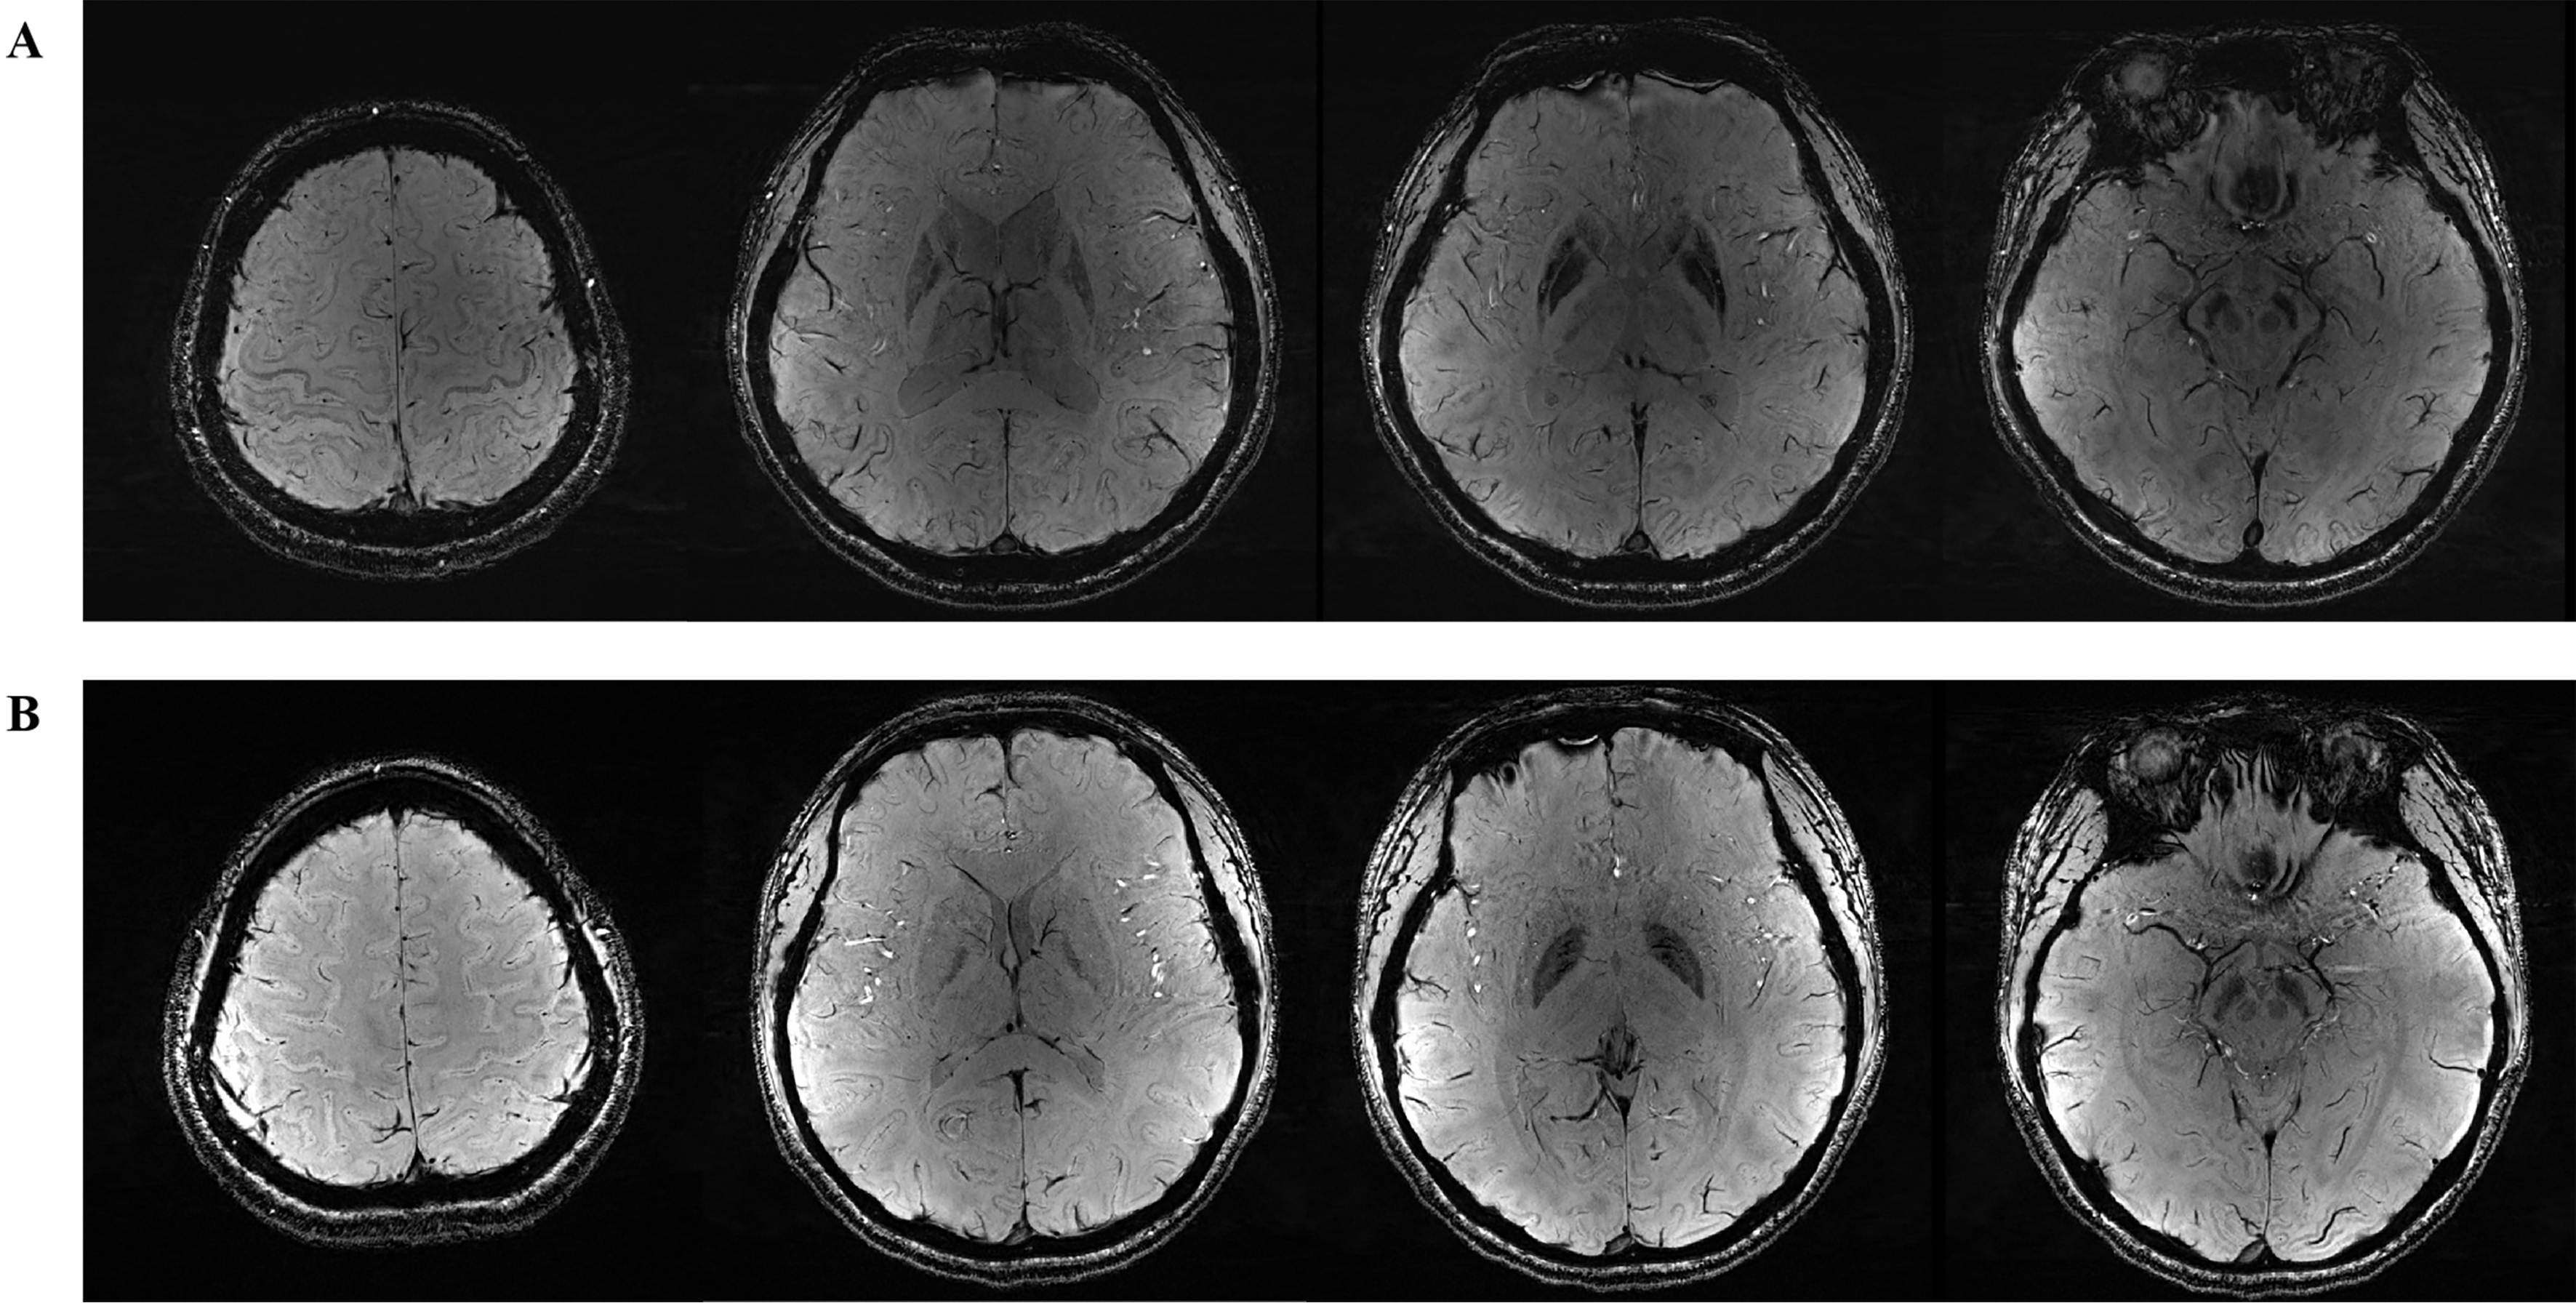

For brain MRI, a 3.0T scanner (Trio; Siemens) was used [Figure 3A and B]. Volumetric analysis (mm3) was conducted using Voxel-based morphometry-the methods[20]. QSM (ppm) was performed using a 3D axial multi-echo GRE sequence to assess iron deposition in specific brain regions[21]. Individualized brain masks were extracted from T1-weighted structural images and then registered to the QSM image space. The QSMbox toolbox (https://gitlab.com/acostaj/QSMbox) was used to compute QSM. Finally, statistical analysis was performed using susceptibility maps referenced to cerebrospinal fluid (CSF). Both the brain volume and QSM analyses encompassed 17 regions, including the left and right cerebellum cortex, thalamus proper, caudate, putamen, pallidum, hippocampus, amygdala, accumbens area, and brainstem.

Figure 3. SWI in brain magnetic resonance imaging. (A) Wilson’s disease patient; (B) Healthy control. SWI: Susceptibility weighted imaging.